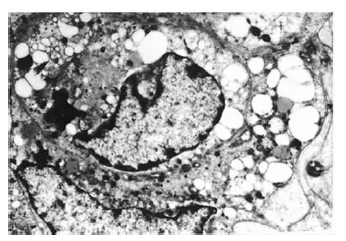

2 结 果 2.1 培养神经元的生长动态及鉴定(图 1)![]() | 图 1 正常培养9 d 的海马神经元( 40 × 10) |

细胞接种24 h 后基本贴壁,2~3 d长出突起的细胞增多,4~5 d胞体进一步铺展,6~7 d胞浆出现丰富而明显的尼氏体,细胞间生长密集,加入阿糖胞苷后细胞背景渐清晰,存活细胞胞体饱满,呈三角形或多边形,胞核圆、大,核仁清晰可见,突起较粗,呈双极、三极或多极,细胞间突起相互交织。8~12 d达高峰,2~3 周后逐渐衰退。尼氏染色可见神经细胞胞浆富含蓝色颗粒,胞核及核仁被染成蓝紫色,突起被染成淡蓝色;胶质细胞则无丰富的胞浆颗粒及清晰深染的核仁。